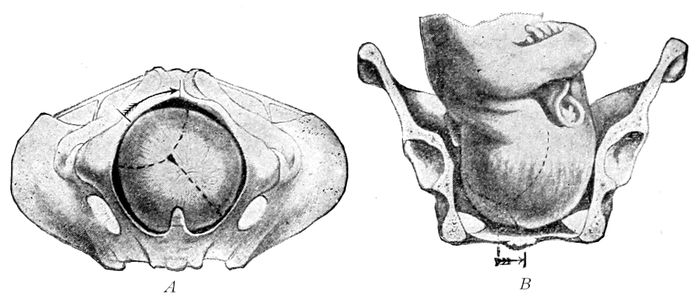

Fig. 22 A.—Child’s head at term (from side), showing diameter. (American Text Book.)

Fig. 22 B.—The child’s head at term (from above), showing diameters and fontanelles. (American Text Book.)

46The fœtal skull at maturity (at term) is still incompletely ossified. The bones are thin and pliable and

separated at their edges by intervals of unossified membrane

which form the sutures and fontanelles. Thus

the skull is compressible to a slight degree and capable

of much change in shape. It can be measurably moulded

by the uterine contractions to suit the pelvis.

In front, the two coronary sutures meet the frontal

and sagittal sutures to produce a kite-shaped figure,

called the large or anterior fontanelle, or the bregma.

Behind, the lambdoidal suture meets the sagittal suture

to form the small or posterior fontanelle.

The large fontanelle is made up of four bones and

four angles; the small, of three bones and three angles,

and are usually easy to differentiate. Furthermore,

the difference between these fontanelles is of great importance

in labor, since by it the observer is enabled to

determine the position of the head. In America, the

shape of the head is that of an ovoid with the long

diameter anteroposterior (Dolico-cephalic). Thus it

happens that when the head is completely flexed, the

smallest diameters are presented for delivery.

The important diameters of the head, with their measurements

and names, are as follows:

Nape of neck to center of bregma, 9.5 cm.—Suboccipito-bregmatic

diameter. Occipital protuberance to root

of nose, 11.25 cm.—Occipito-frontal diameter. Between

the eminences of parietal bones, 9.25 cm.—Biparietal

diameter. Between anterior ends of coronal sutures, 8

cm.—Bitemporal diameter.

The smallest circumference is that of the suboccipito-bregmatic

plane, which comes into relation with

the brim of the pelvis when the flexion of the head is

complete. It measures 27.5 centimeters.